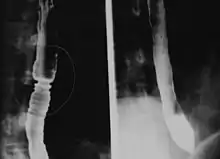

Radiologically, the term "ringed esophagus" has been used for the appearance of eosinophilic esophagitis on barium swallow studies to contrast with the appearance of transient transverse folds sometimes seen with esophageal reflux (termed "feline esophagus").[11]

Endoscopically, ridges, furrows, or rings may be seen in the esophageal wall. Sometimes, multiple rings may occur in the esophagus, leading to the term "corrugated esophagus" or "feline esophagus" due to similarity of the rings to the cat esophagus. Presence of white exudates in esophagus is also suggestive of the diagnosis.[12] On biopsy taken at the time of endoscopy, numerous eosinophils can be seen in the superficial epithelium. A minimum of 15 eosinophils per high-power field are required to make the diagnosis. Eosinophilic inflammation is not limited to the esophagus alone, and does extend through the whole gastrointestinal tract. Profoundly degranulated eosinophils may also be present, as may micro-abscesses and an expansion of the basal layer.[3][9]